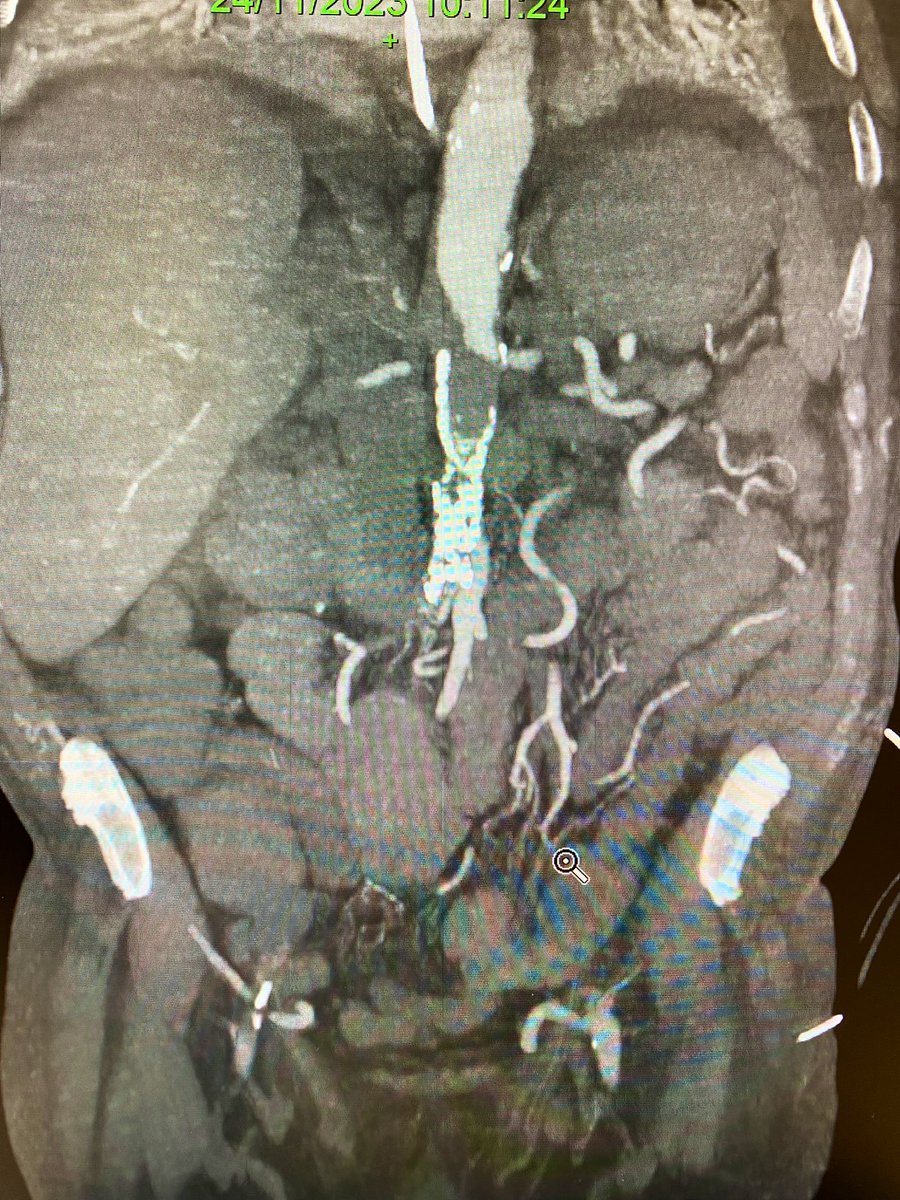

Type II endoleak with progressive sac enlargement. The first #inthebucket of 2024! 🗑️ #veterosurgery

“Get together”…sometimes “Open Repair” need to be done after/with EVAR. Surgical option. Type I refractory endoleak. FEVAR not possible due to tortuosity, calcification and diameter of the external iliac.#vascularsurgery #hospitaldasclinicasribeiraopreto #aorta #aneurysm #usp

Type IA 120x130mm symptomatic. #veterosurgery #inthebucket